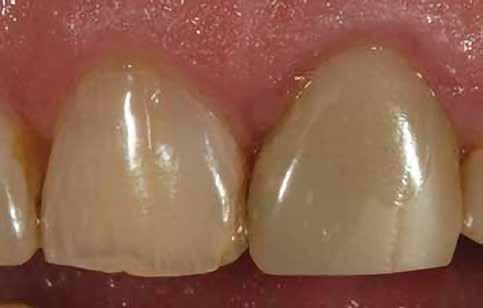

Egy páciens elégedetlen volt a 8. fog incisofaciális felszínén lévő kéthetes restaurációval, mert úgy gondolta, hogy a központi metszőfogak nem illeszkednek egymáshoz. A vizsgálat során megállapították, hogy bár az egyszínű kompozit valóban megegyezett a fog alapszínével, további színre (árnyalatra) volt szükség a szomszédos fog utánzásához (4. ábra).

A fogakat nehéz latexmentes gumidámmal (Isodam, 4D Rubber) izolálták. A meglévő kompozitot eltávolítottuk; egy kromatikus mikrotöltésű kompozitot helyeztünk fel, és egy fehér színt (Creating Color, Cosmedent) vittünk fel egy #8-as K-résszel, vízszintes mozgással, hogy a vízszintes mintázatot lemásoljuk (5. ábra), ezután egy akromatikus mikrotöltésű kompozitot adtak hozzá. A 6. ábra az azonnali posztoperatív eredményt mutatja, a 7. ábra pedig a négyéves utóvizsgálatot, amely a mikrotöltött kompozit megmaradt fényét mutatja.